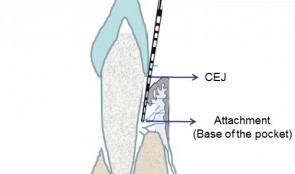

Examiner Standardization And Calibration

based on the book chapter by Hatice Hasturk and Mary Ann Cugini Summary The emphasis of this chapter is on examiner--therapist alignment and standardization when conducting controlled clinical trials, especially those with multicenter settings. It begins with definitions of various key research team members and follows by giving specific advice on assessing regeneration by periodontal and bone probing, with reference to parameters relating to probing depth, the cemento--enamel junction, gingival margins, keratinized gingiva, tooth mobility, clinical attachment and alveolar bone gain. The authors explain the relevance of bleeding, plaque and gingival health indices, and the stress the importance of selecting suitable reference points and scoring scales. Detail is provided on the techniques of mucogingival regeneration, alveolar ridge augmentation and implant insertion, and factors such as wound healing. There are protocols for alignment and agreement sessions, and recommendations for conducting regular realignment sessions, with tailored training and calibration, in order to ensure consistency in skills and performance of the team, in data capture and interpretation, and in use of instruments and scoring systems. Practical tips are given on various aspects of the study including set up and timings, examiner--observer agreement and inter-class correlation, with guidance on organizing the research team, assessment plans and statistical analysis. The overall aim of the chapter is to ensure production of high-quality data with minimal uncertainty. Open full-text PDF (1.4 MB) -